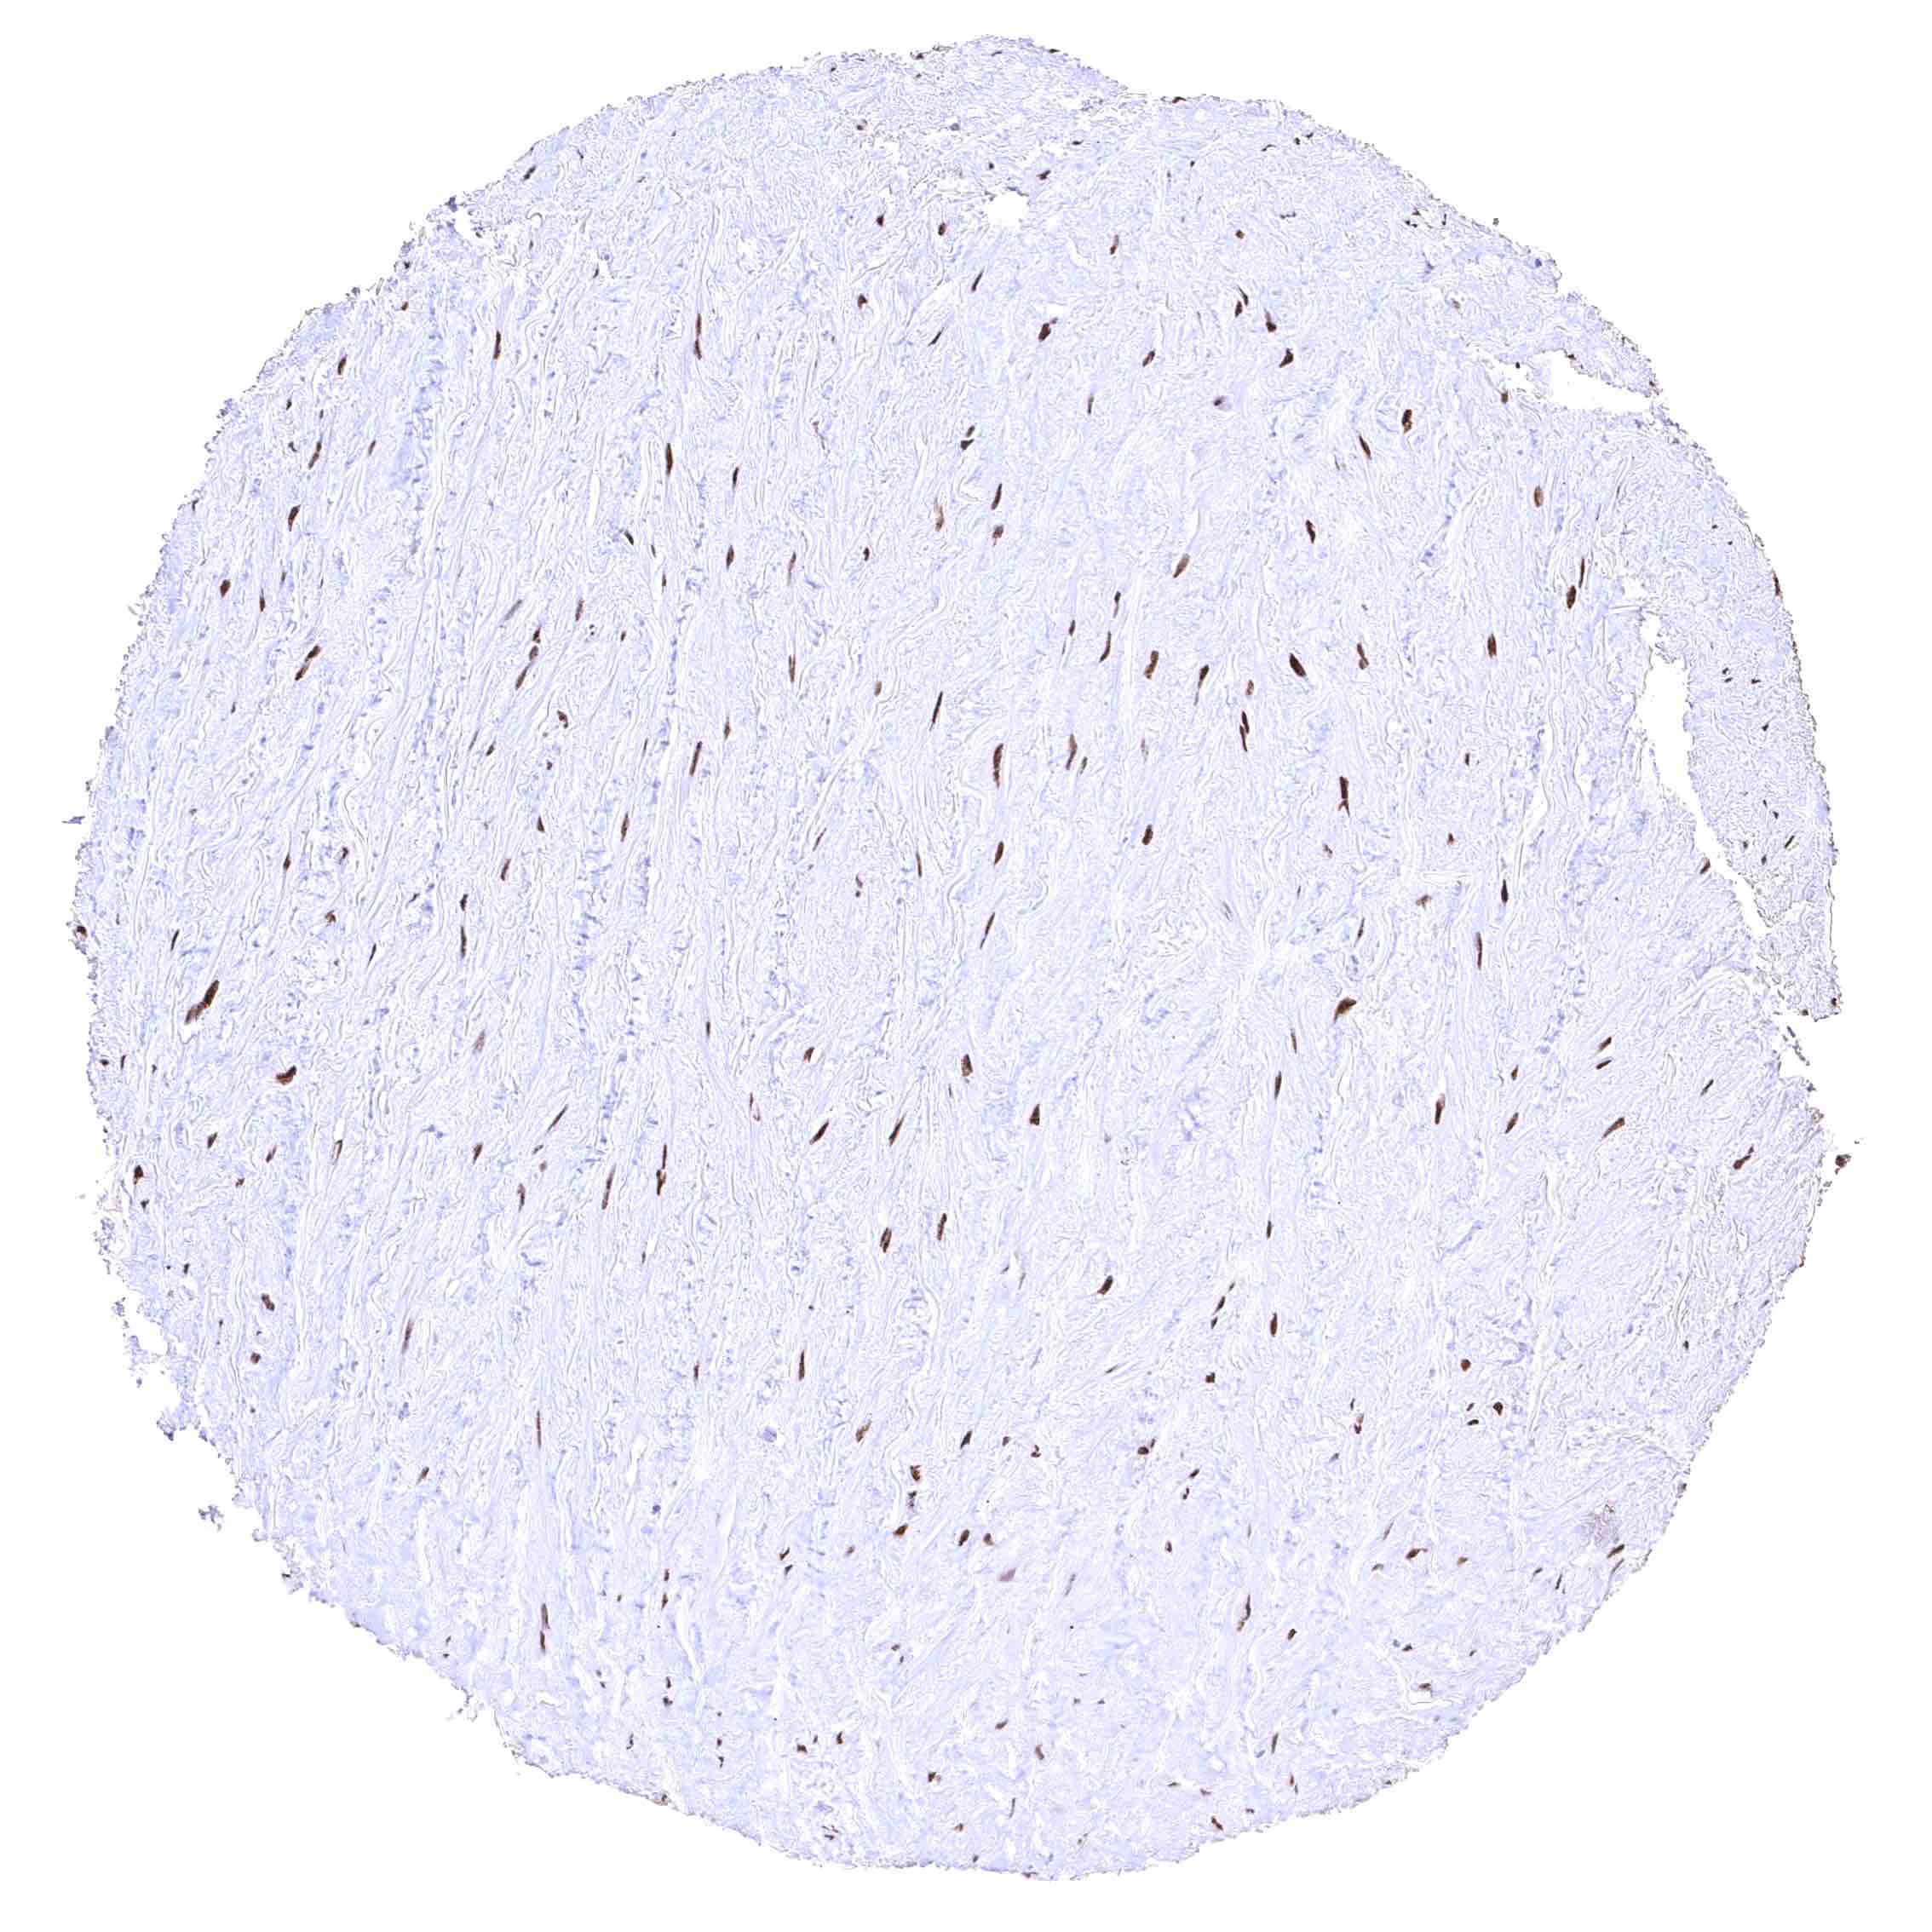

Aorta, media